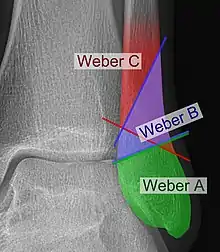

The Danis–Weber classification (often known just as the Weber classification) is a method of describing ankle fractures. It has three categories:[1]

- Type A

Fracture of the fibula distal to the syndesmosis (the connection between the distal ends of the tibia and fibula). Typical features:

- Type B

Fracture of the fibula at the level of the syndesmosis. Typical features:

- Type C

Fracture of the fibula proximal to the syndesmosis. Typical features:

Categories B and C imply a degree of damage to the syndesmosis itself (which cannot be directly visualised on X-ray). They are inherently unstable and are more likely to require operative repair to achieve a good outcome. Type A fractures are usually stable and can be managed with simple measures, such as a plaster of paris cast.